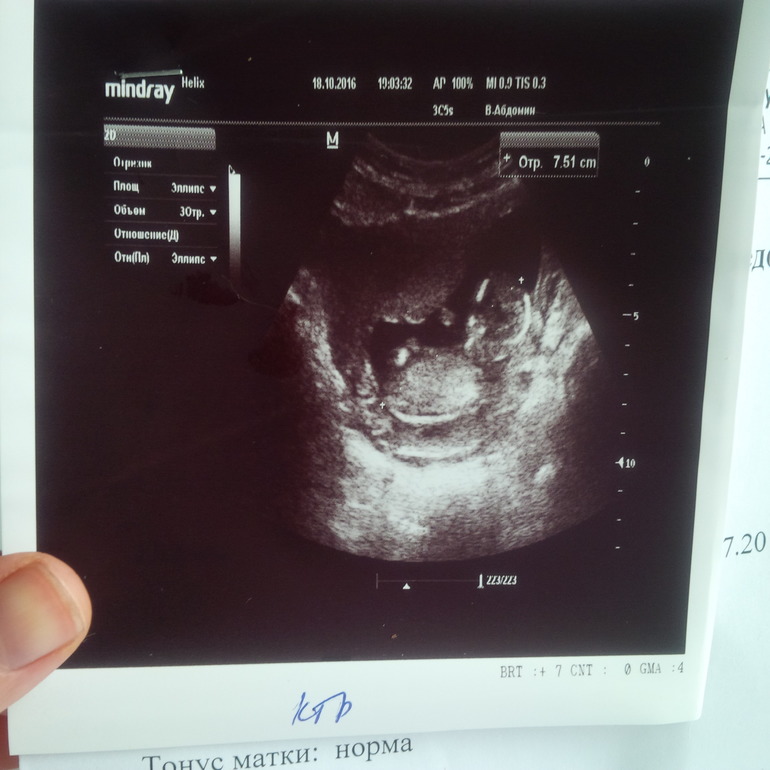

Пишу и обалдеваю (точнее не скажешь). Муж сегодня за завтраком снова повторил: "У нас же малыш будет!" и расплылся в кошачьей улыбке. На холодильнике уже висит первое фото с первого скрининга (его, кстати, все-таки прошла в "Меди", рядом с домом). Результаты хорошие. Малявка наш на 3 дня опережает те сроки, что по месячным. 7 см 51 мм - уже ого-го человек!Снова не спал и вертелся. Кровь тоже (тьфу-тьфу-тьфу) хорошая. Риски низкие. Дай то Бог. (далее по кат)